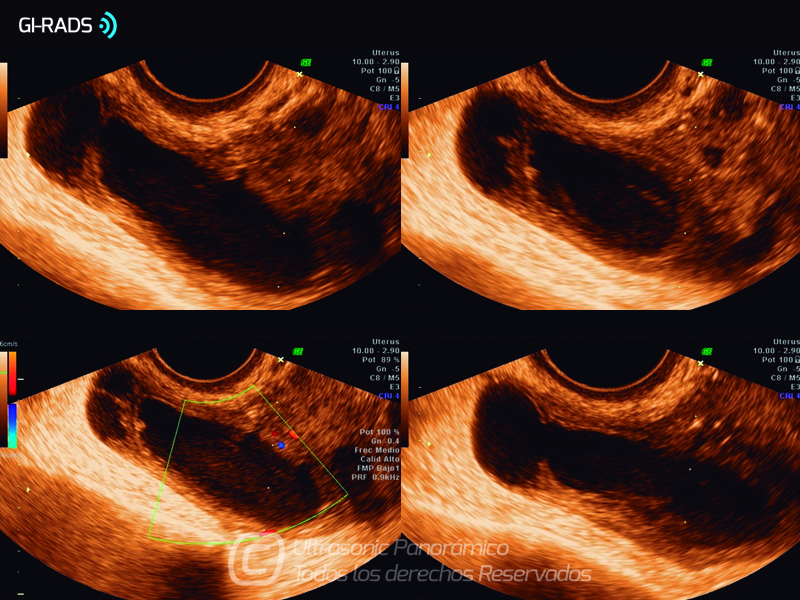

Patologías Benignas – Abceso Tubo Ovárico

• Patologías Benignas – Abceso Tubo Ovárico